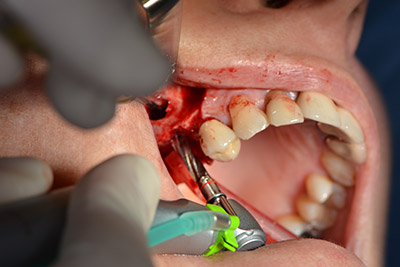

Acto seguido, se coloca el implante y se estructura el hueso. Dado el tamaño del aumento, en el caso que nos ocupa se utilizó hueso autógeno, que había surgido como virutas de fresado en el implante 16 y en la fenestración 14 y se había recogido con un colector óseo, y se combinó con material de reemplazo óseo.

Una membrana reabsorbible formó la barrera en sentido bucal y cubrió el aumento. Por último se procedió a la sutura de modo que no penetrara saliva (figuras 15 a 19).